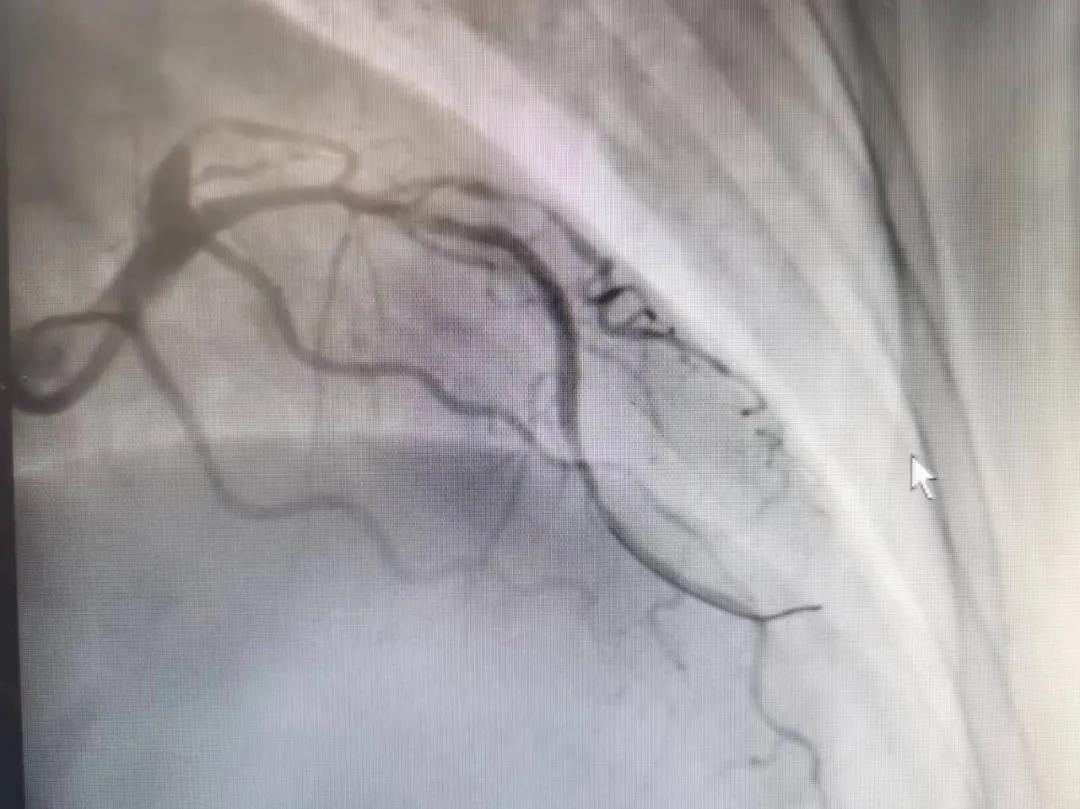

病人是位六十多歲的女性患者,有長(zhǎng)期高血壓病史,1個(gè)月前開(kāi)始出現(xiàn)胸悶胸痛,口服藥物治療效果不佳,經(jīng)朋友介紹,來(lái)到市二院心血管內(nèi)科。入院后完善冠狀動(dòng)脈造影提示:前降支全程彌漫性狹窄伴鈣化,最重95%,回旋支狹窄約85%,右冠脈全程狹窄伴鈣化,最重60%。血管內(nèi)超聲顯示右冠脈開(kāi)口面積3.36mm²,可見(jiàn)環(huán)形鈣化,考慮患者病變程度重、鈣化明顯,常規(guī)器械無(wú)法實(shí)現(xiàn)病變的良好預(yù)處理,且有很高的冠脈穿孔、血管夾層的風(fēng)險(xiǎn)。

術(shù)前